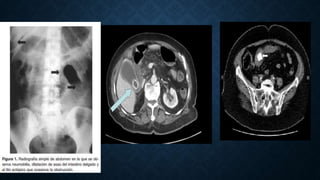

RX DE AMBDOMEN: 40 – 50%

. TRIADA DE RIGLER: Obstrucción intestinal parcial o completa, aire en la vía

biliar y visualización directa del cálculo

TAC ABDOMINAL: 75-85%

• Lassandro y colaboradores compararon el valor clínico de la placa simple de

abdomen, la ecografía abdominal y el TAC abdominal en el diagnóstico de 27 casos

de íleo biliar, y encontraron que la triada de Rigler está presente en 14,81% en la

placa simple de abdomen, 11,11% en la ecografía abdominal, y en 77,78% en el TAC

abdominal

• #11 Fig. 4: Gran litiasis biliar (marcada con flecha) en paciente asintomática. Corte axial de la TAC que muestra la presencia de un cálculo impactado en el intestino